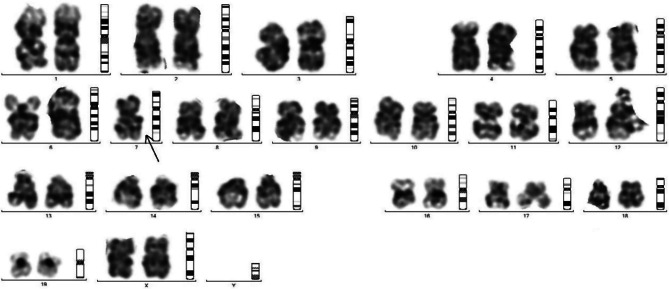

Results: Treatment with endosulfan at the dose of 3.5 mg/Kg body weight caused a higher degree of degeneration in the reproductive organ of Swiss albino mice . Treatment by this pesticide generated degeneration in long duration of dosage for 3,5 and 7 weeks. Ovaries of endosulfan administered groups showed degenerated germinal epithelium, Graffian follicles and corpus luteum. In testis of endosulfan treated mice, microscopic examination showed that there is significant damage and reduction in the tissue of seminiferous tubules and primordial germ cells. High degree of degeneration caused the disarrangement and deformation of spermatogonia with the decrease in the number of Sertoli cells. Biochemical and hormonal properties was also affected by endosulfan treatment. There was significant 5 folds decrease in the testosterone value of endosulfan in 7 weeks treated mice in comparison to control (p < 0.0001) and similarly there was significant elevation in the estrogen levels found in 7th week endosulfan treated mice. It also influenced the level of free radicals as there was significant decrease (p < 0.0001) in the value in catalase levels in 7 weeks endosulfan treated male and female mice, while significant (p < 0.0001) increase in the values of lipid peroxidation levels as 8 folds and 10 folds in 7 weeks endosulfan treated male and female Swiss albino mice respectively. This study hence speculates that the endosulfan exposed population are at the risk of reproductive health hazards.

Conclusions: The present study thus concludes that, endosulfan after 7 weeks of exposure caused significant reproductive damage to both male and female Swiss albino mice groups. Moreover, the karyotyping study also correlated the genotoxic damage in the mice.